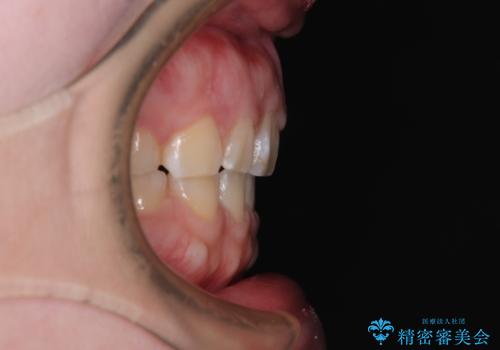

- 出っ歯と口の閉じにくさ、デコボコを気にして来院された患者様です。

口元の突出感を改善するため、上下左右第一小臼歯4本の抜歯を行い、ワイヤー装置による矯正治療を行うこととしました。

抜歯矯正を行ったことで、顎先のつっぱり感や口元の閉じにくさを解消することができました。